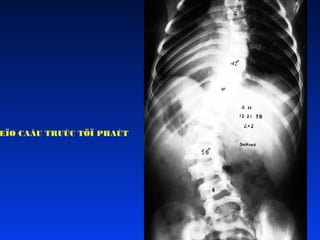

Veïo coät soáng caáu truùc töï

phaùt

Veïo coät soáng thaét löng ôû

ngöôøi tröôûng thaønh

2 nguyeân nhaân chính:

1. Tieán trieån VCS luùc thieáu nieân

2. Thoùai hoùa cs thaét löng thöôøng sau

tuoåi 50: do ñóa thoaùi hoùa hay do

loõang xöông

Tuy nhieân trong haàu haát caùc ca thì

khoâng roõ nguyeân nhaân